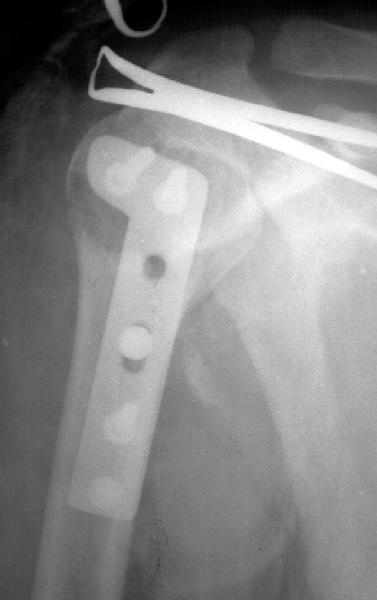

Мужчина 25 лет 16 августа 2002 г. в автоаварии получил перелом шейки плеча (снимок 1); 5 сентября в городской больнице выполнен остеосинтез пластинкой (снимок 2).К настоящему времени попал к нам на разработку ввиду выраженной контрактуры плечевого сустава. В течение последнего месяца беспокоят умеренные боли в области плечевого сустава, усиливающиеся при разработке, еще и торчит край пластинки. Нынешняя рентгенологическаякартина на снимках 3 и 4. Головка плеча уменьшается, сращение сомнительное.Кроме удаления пластинки, что еще на сегодня целесообразно сделать?Заранее спасибо.

I think the AVN is at least stage 3 with deformity of the head. I would advise a removal of implant and a cementless humeral head replacement. Or if you have the experience and the implant, as well as adequate bone stock, maybe a resurfacing prosthesis like the Copeland shoulder. I am not sure if you can do it one or two stages. You can perhaps do it in one stage if there is no sign of infection and if the patient condition allows it. You should not worry too much about age since this is a non

The current xrays indicate failure of the implant with losening. I would make sure there was no evidence of infection ( exam,ESR,CRP etc.) . I would agree with implant removal . I think this would be a suitable case for a circular ring fixator and compression, either a standard IIizarov or Taylor Spatial frame would be appropriate. I note from your previous cases that you have a high level of experience with this method.